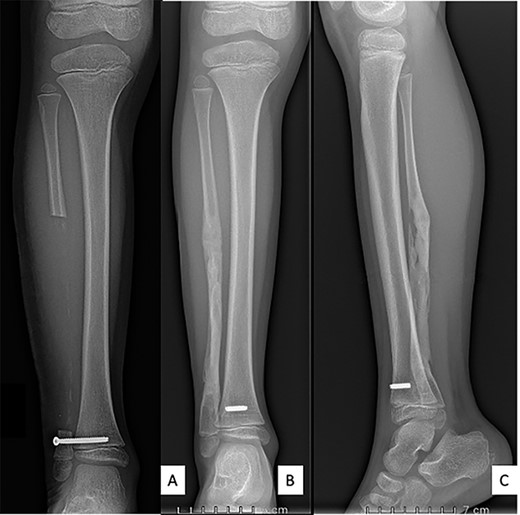

All bacteriological samples were negative. Anatomopathological analysis showed islands of cells that were positive for cytokeratin AE1/A3 but negative for CD68 and CD138 (Fig. 5). These findings argued for the diagnosis of OFD/AD rather than OFD. The day after the procedure, the child was allowed to walk with full weight bearing. The preservation of periosteum allowed rapid reconstruction of fibula (Fig. 6).

Anteroposterior radiograph and lateral view after right fibulectomy. (A): at 2-postoperative-weeks: preservation of the periosteum allowed progressive formation of new bone. (B) and (C): at 1-postoperative-year: a new fibula is reappeared. The syndesmosis screw broke with weight-bearing and only the fibular part of the screw was removed.